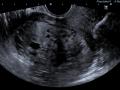

Tag: ultrassonografia transvaginal

Diagnóstico por imagem em ginecologia - Quinto ano medicina